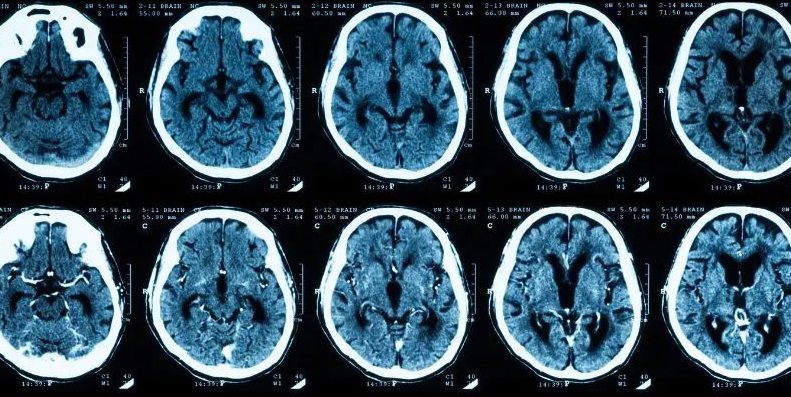

Brain Stroke in Young Adults : कुछ दशक पहले तक ब्रेन स्ट्रोक को बुढ़ापे की बीमारी माना जाता था लेकिन अब यह धारणा पूरी तरह बदल चुकी है। एक नई और डराने वाली रिसर्च के अनुसार भारत में ब्रेन स्ट्रोक का शिकार होने वाला हर सातवां मरीज 45 साल से कम उम्र का है। नेशनल सेंटर फॉर डिजीज इंफॉर्मेटिक्स एंड रिसर्च (NCDIR) द्वारा किए गए इस शोध ने स्वास्थ्य विशेषज्ञों की चिंता बढ़ा दी है।

'इंटरनेशनल जर्नल ऑफ स्ट्रोक' में प्रकाशित इस अध्ययन में 2020 से 2022 के बीच देश के 30 बड़े अस्पतालों के 35,000 मरीजों का डेटा विश्लेषण किया गया।

युवाओं की संख्या: कुल मरीजों में से 13.8% लोग 45 साल से कम उम्र के थे।

पुरुषों पर खतरा: स्ट्रोक के शिकार युवाओं में 60% से अधिक पुरुष शामिल हैं।

इलाज में देरी: करीब 40% मरीज स्ट्रोक आने के 24 घंटे बाद अस्पताल पहुंचे। सही समय पर इलाज न मिलने के कारण 30% मरीजों की मौत हो गई।